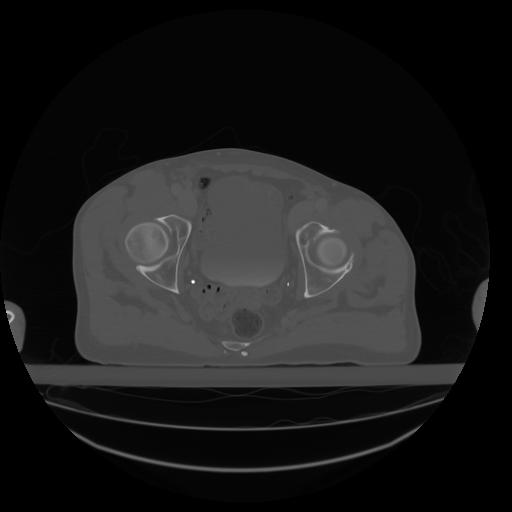

27 CUERPO,CE,Axial,3.0,CUERPO,,